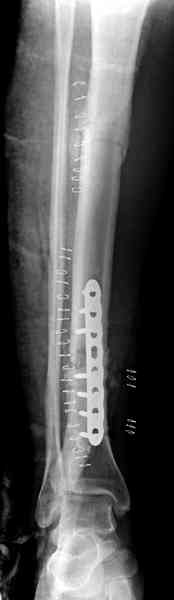

conference мы разбирали похожий случай, ложный сустав большеберцовой кости после резекции опухоли.

К нашему онкологу-ортопеду обратился больной с жалобами на боли в голени, из рассказа - год назад была сделана биопсия большеберцовой кости, но название заболевания "не запомнил”.

Оперирован в военном госпитале с заменой сегмента

аллокостью большеберцовой кости и после демобилизации явился для постоянного наблюдения по месту жительства.

В литературе "A Classic Adamantinoma Arising from

Osteofibrous Displasialike Adamantinoma in the Lower Leg: A case report and Review of the Literature похожие снимки.

Наши имели проблему со сращением, пришлось им сделать динамизацию, дополнительную аутопластику.

Снимки представлены.